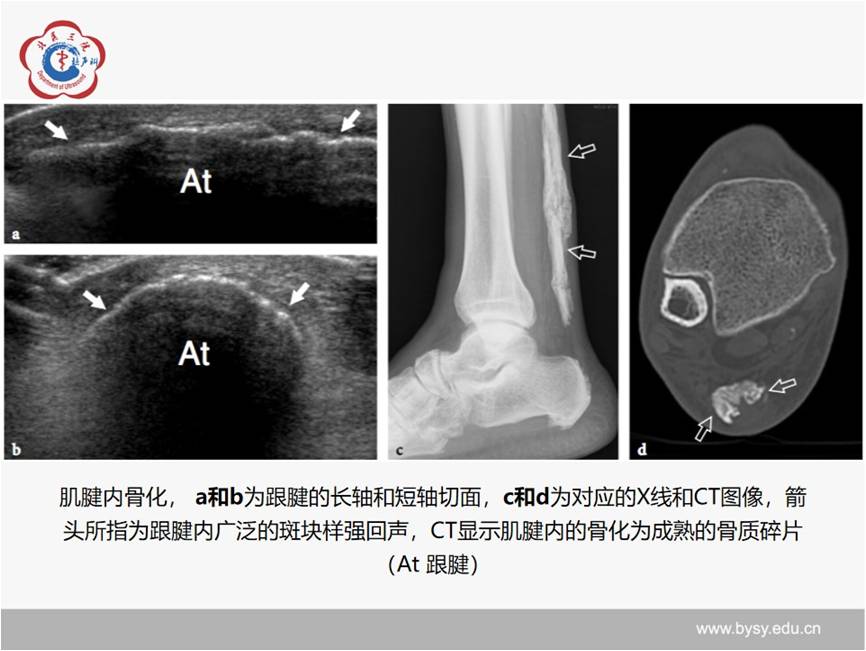

【经典超声书籍解读】肌肉骨胳超声诊断之肌腱病与部分撕裂